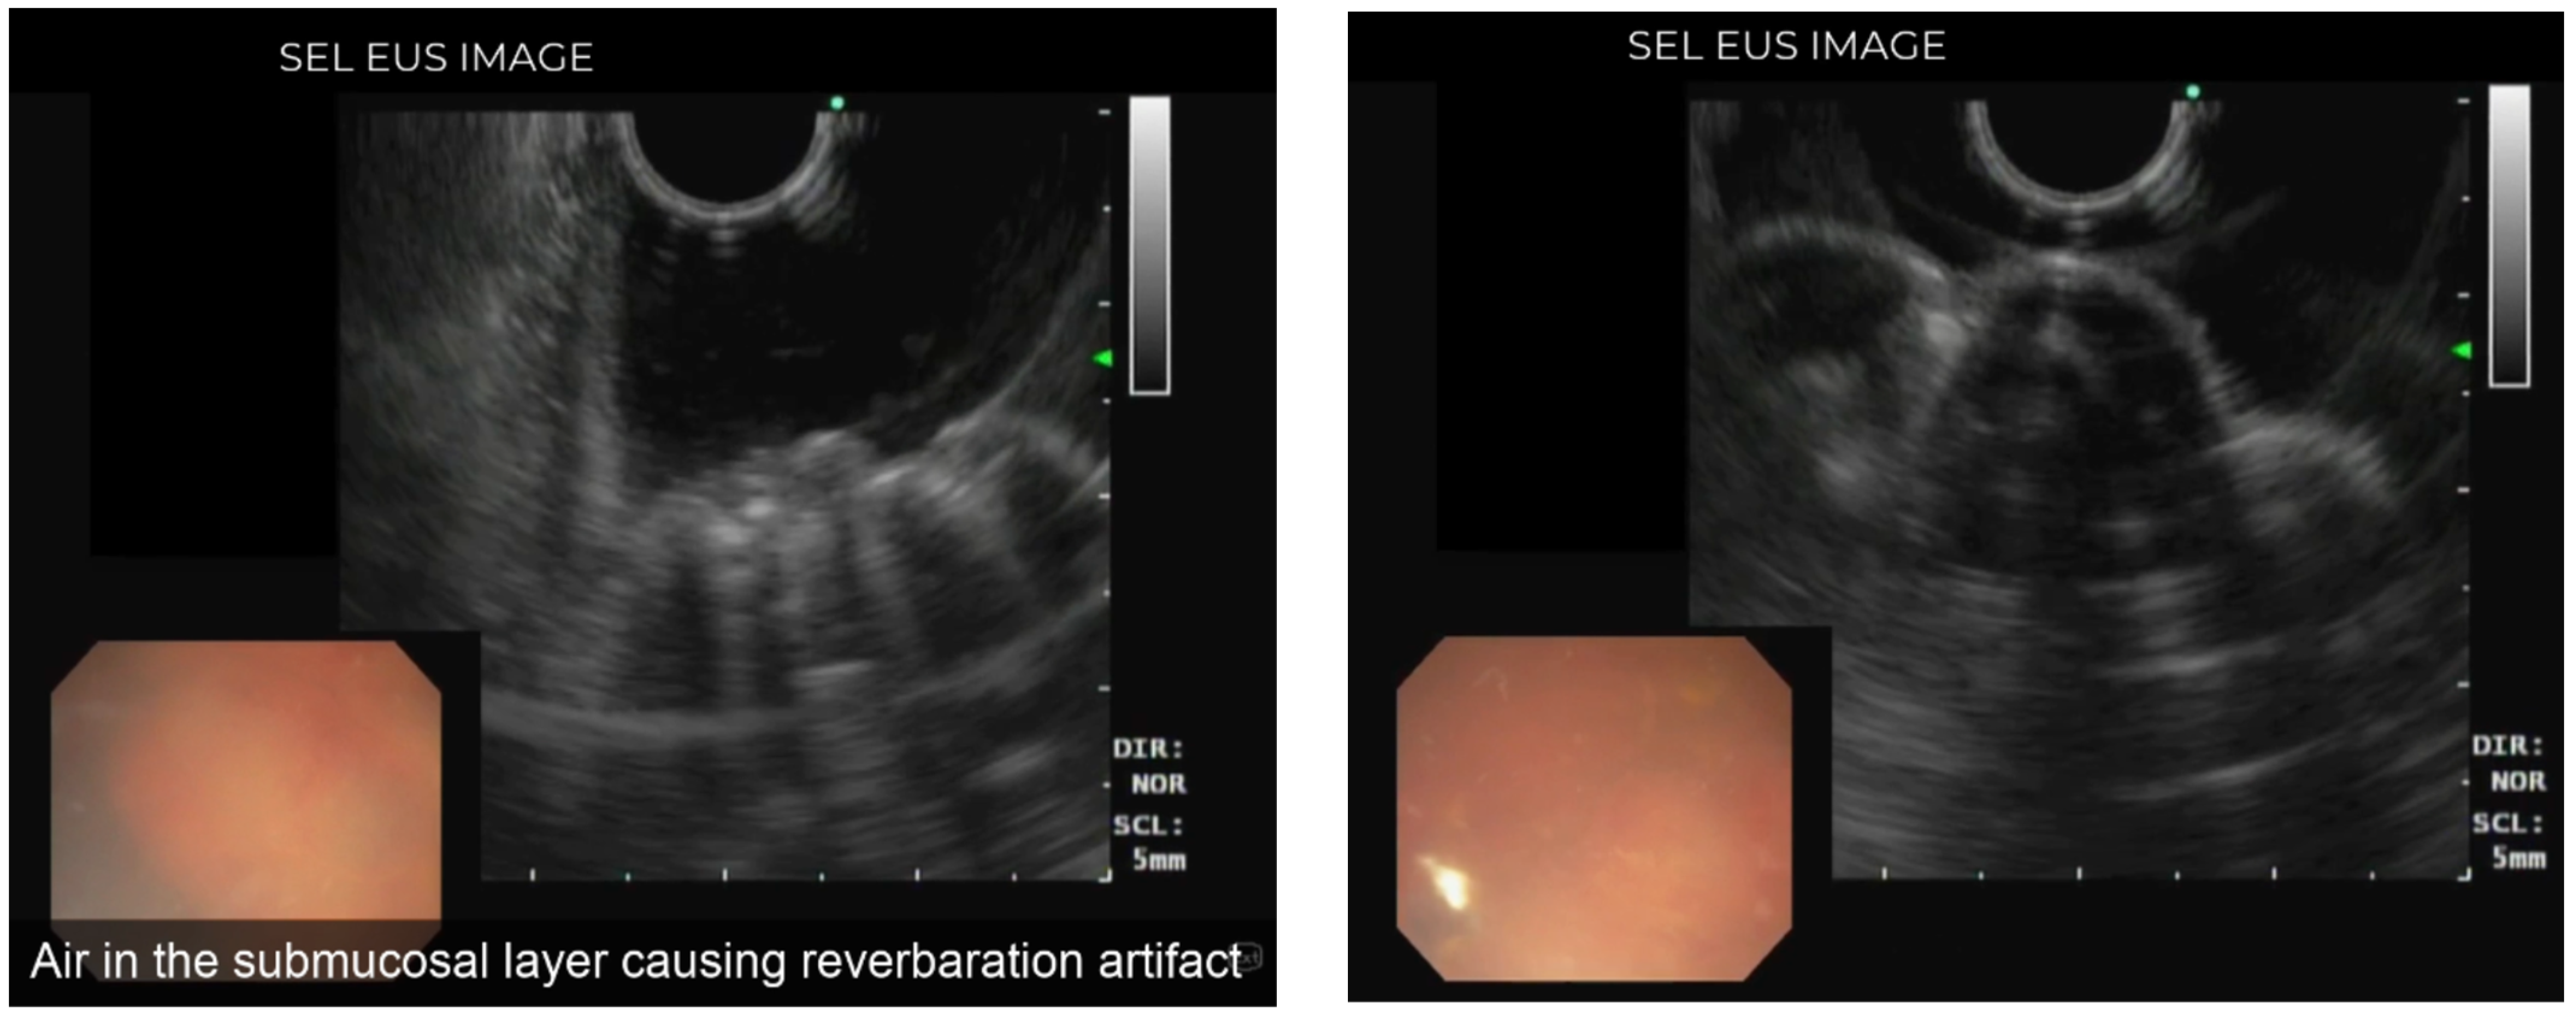

Endoscopic Ultrasound View of Pneumatosis Cystoides Intestinalis

- Castro-Poças, F.; Araújo, T.; Pedroto, I. Endoscopic ultrasound of pneumatosis cystoides intestinalis. Endoscopy 2015, 47 (Suppl 1), E274. [Google Scholar] [CrossRef] [PubMed]

- Shimada, M.; Ina, K.; Takahashi, H.; Horiuchi, Y.; Imada, A.; Nishio, Y.; Ando, T.; Kusugami, K. Pneumatosis cystoides intestinalis treated with hyperbaric oxygen therapy: Usefulness of an endoscopic ultrasonic catheter probe for diagnosis. Intern Med. 2001, 40, 896–900. [Google Scholar] [CrossRef] [PubMed]